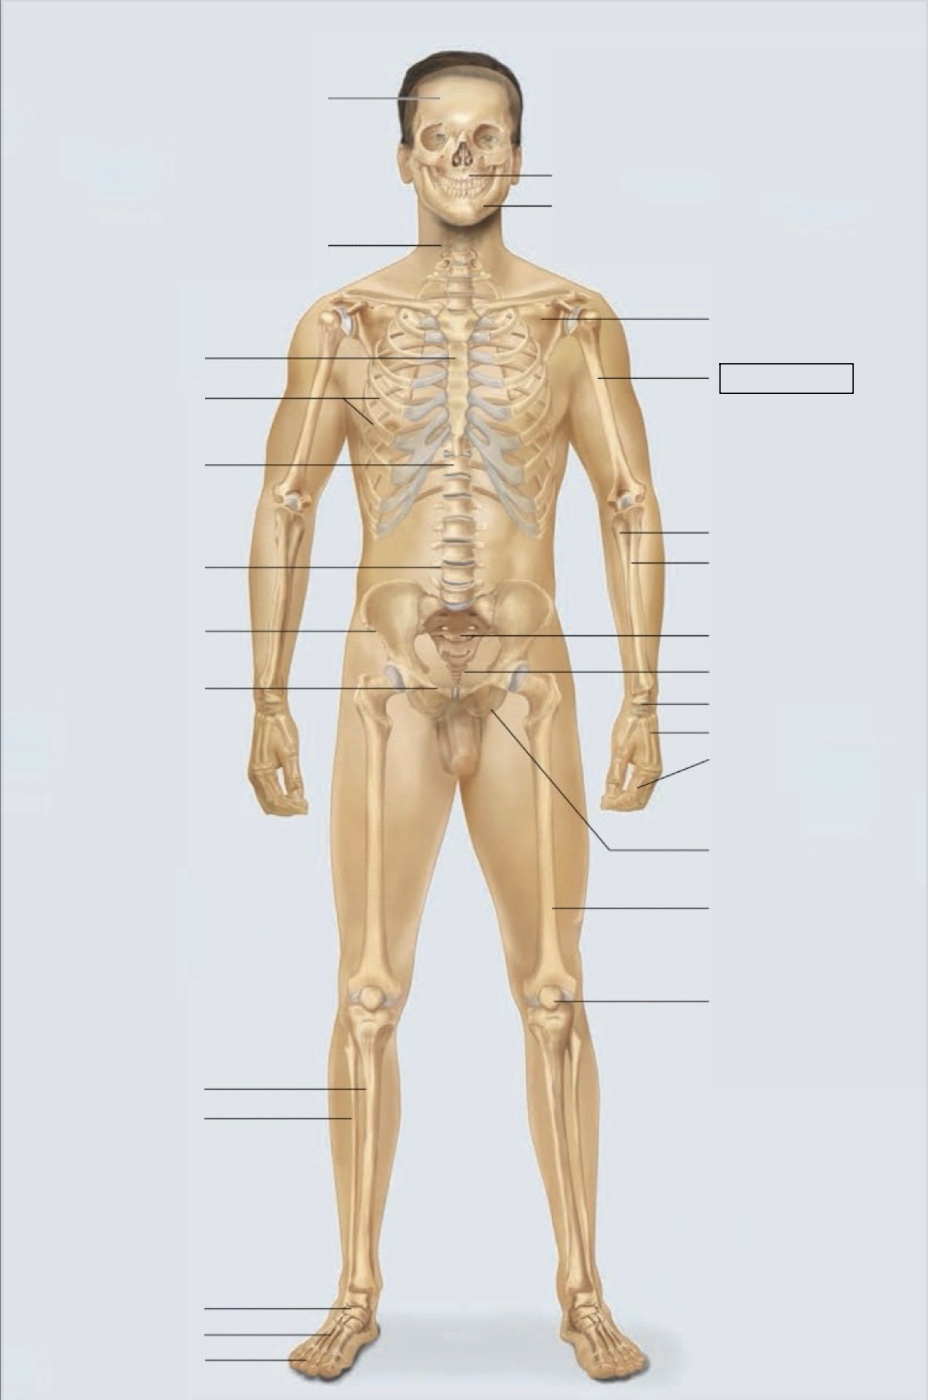

maxilla

mandible

scapula

humerus

ulna

radius

sacrum

coccyx

carpals

metacarpals

phalanges

ischium

femur

patella

phalanges

metatarsals

tarsals

fibula

tibia

pubis

ilium

lumbar vertebrae (L4)

thoracic vertebrae (T11)

ribs

sternum

cervical vertebrae

skull